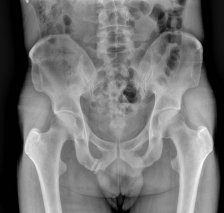

¹æ»ç¼± °Ë»ç :  ÁÂÃø °í°üÀý  ¿ÜÃø ¿Í¼ø°ú °üÀý³¶ºÎÀ§  ¼®È¸È­(+)(»çÁø10) * »çÁøÀ» Ŭ¸¯Çϸé ÇØ´ç »çÁøÀÌ º¸ÀÔ´Ï´Ù.

5ÁÖ ÈÄ  ÃßÀû°Ë»ç ¹æ»ó¼± °Ë»ç¿¡¼­ ¼®È¸°¡ °ÅÀÇ ¿ÏÀü ¼Ò½Ç µÊ(»çÁø 11)..